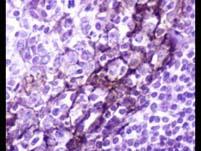

问题 可合并白血病的淋巴瘤主要是()

选项 A.淋巴细胞为主型霍奇金淋巴瘤 B.小淋巴细胞性淋巴瘤 C.免疫母细胞性淋巴瘤 D.伯基特淋巴瘤 E.骨髓瘤

答案 B